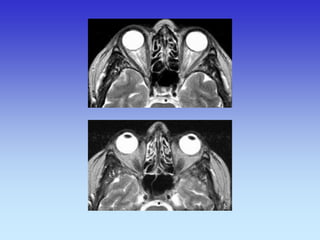

CT- ORBITA

TRANSVERZALNI SLOJ

CT- SINUSA

KORONARNI SLOJ

1.Retroorbitalna mast

2.M. Rectus medialis

3.Leća

4.M. Rectus lateralis

5.Optički živac

5

1

3

2

4